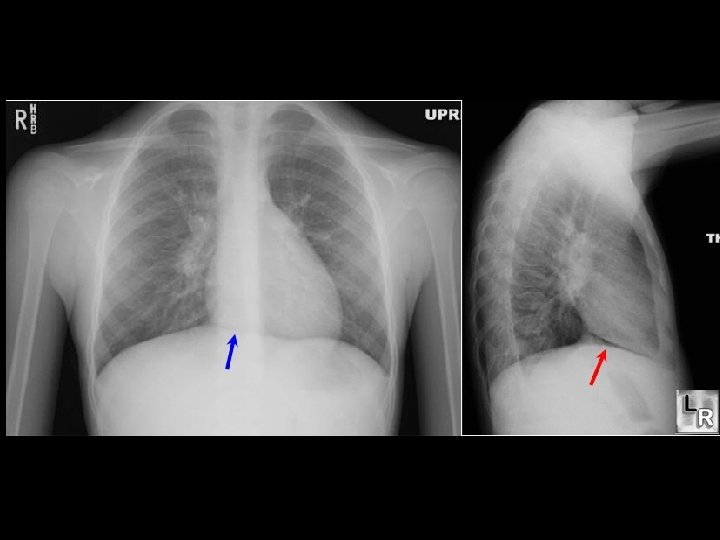

Heimildir n n Moore KL, Dalley AF. Clinically oriented anatomy. Lippincott Williams and Wilkins. Canada, 1999. http: //content. nejm. org/cgi/content/full/354/11/1177/F 1 http: //www. emedicine. com/ped/topic 1832. htm Sobotta, atlas der Anatomie des Menschen